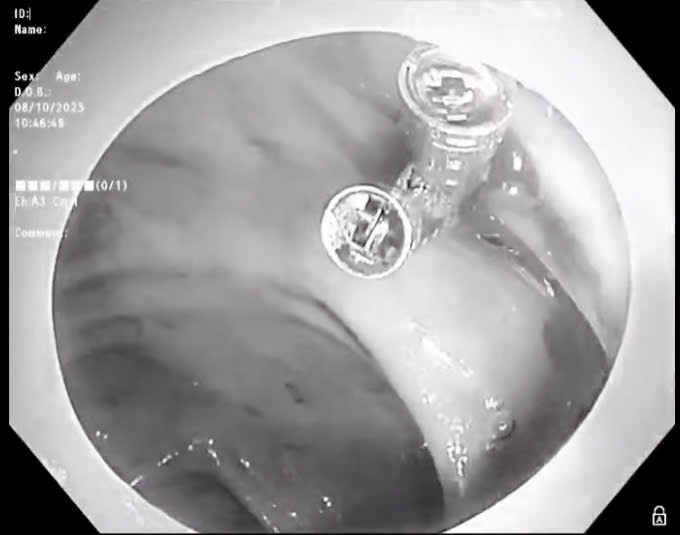

Về đảm bảo hậu cần trong phòng chống dịch, toàn tỉnh có 2 máy Realtime PCR bán tự động triển khai thực hiện xét nghiệm sàng lọc SARS-CoV-2 (trong đó có 1 máy Realtime PCR của Bệnh viện đa khoa tỉnh; 1 máy Realtime PCR của Trung tâm Kiểm soát bệnh tật do tập đoàn Vingroup tài trợ).